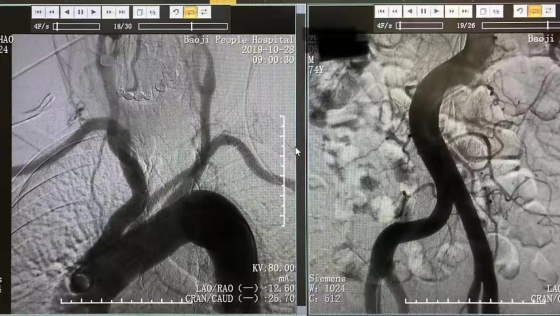

近日,57岁的李先生,因发作性头晕、左侧肢体无力麻木17小时入院,入科后反复短暂性脑缺血(TIA)发作,出现头晕、左侧肢体无力麻木数次,每次发作数分钟后好转,患者及家属非...